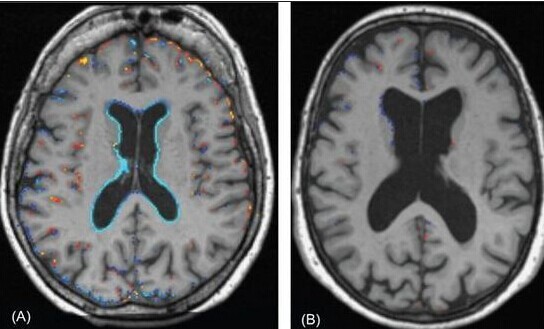

实际上,在一篇Review当中提到[1 ],在临终之前大脑的意识并不是正常时的样子,比如慢性的脑损伤病症,阿尔茨海默症(老年痴呆)有着渐恶性的脑萎缩(呈现巨大的空洞)

科学解释为什么会有回光返照?821 / 作者:UFO外星人爱好者 / 帖子ID:33158

这些病症中偶尔会有稍纵即逝的反弹性脑功能回归,甚至在临终前有颅压回升等现象,但别的脑内的病变比如精神分裂症等,回光返照的指标又完全不同.